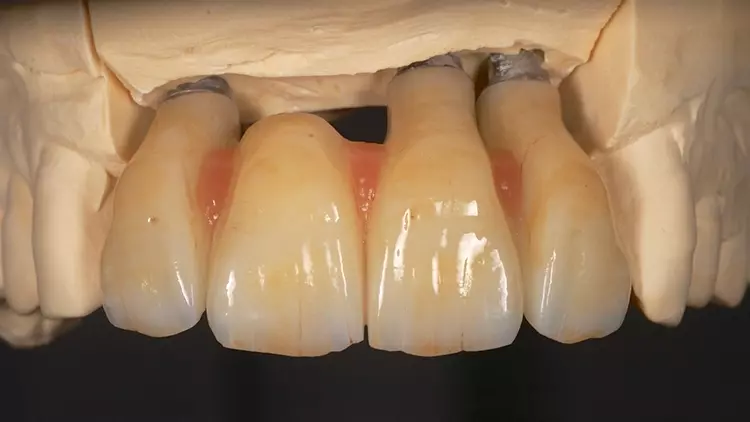

Die Restaurationen fügten sich sowohl klinisch als auch ästhetisch durch ihre spezielle Charakterisierung in die bestehende Patientensituation ein (Abb. 13-15). Auch röntgenologisch konnte eine gute Passform ermittelt werden (Abb. 16).

Der vorliegende Patientenfall beschreibt die Implantatversorgung im Ober- und Unterkiefer-Frontzahnbereich eines älteren Patienten mit einer chronischen Parodontitis und ohne systemische Erkrankungen bzw. ohne eine regelmäßige Einnahme von Medikamenten. Infolge des Attachmentverlusts konnte trotz einer Ridge Preservation mittels Sofortimplantation und einer bukkalen Auflagerung von xenogenem Knochenersatzmaterial insbesondere im Bereich der Interdentalpapillen des Oberkiefers kein ausreichender Weichgewebserhalt in vertikaler Richtung erzielt werden, was auf den Attachmentverlust infolge der Parodontitis zurückgeführt werden kann. Daher war es notwendig, die fehlenden Papillen mittels rosa eingefärbten Zirkonoxids in die Restauration zu integrieren (Abb. 13 und 14).

Der Patient wurde entsprechend instruiert, diese Bereiche täglich mittels Interdentalbürsten zu reinigen. Rezessionen wurden nicht beobachtet, was auf den dicken Phänotyp des Patienten zurückgeführt werden könnte [5]. Trotz der geringen Einschränkungen im Bereich der rot-weißen Ästhetik war der Patient mit dem ästhetischen Gesamtergebnis zufrieden.